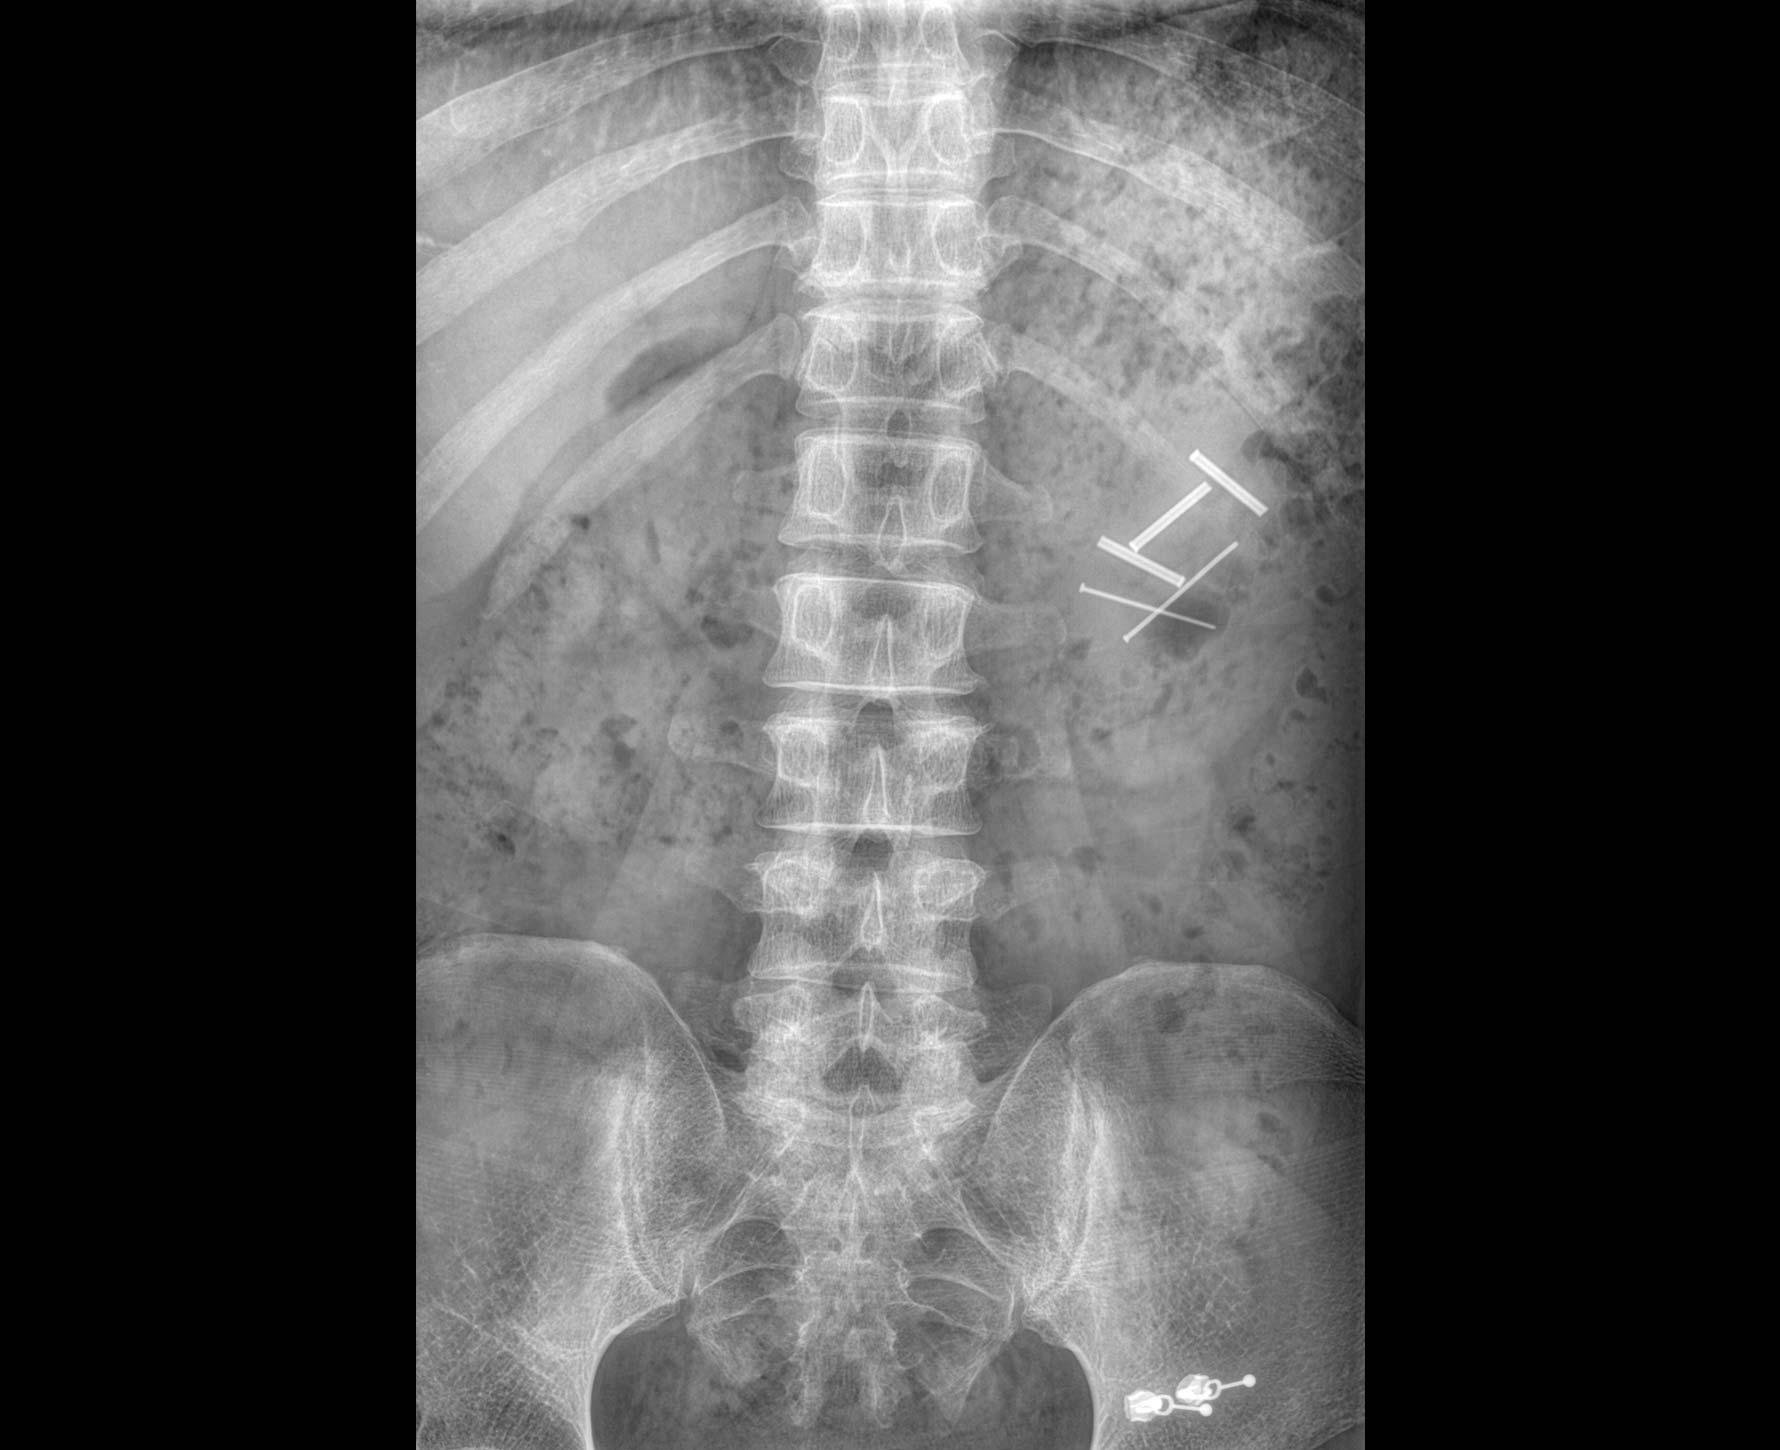

• 标配全身拼接功能

无缝融合处理,保证高质量全景影像。

临床图像